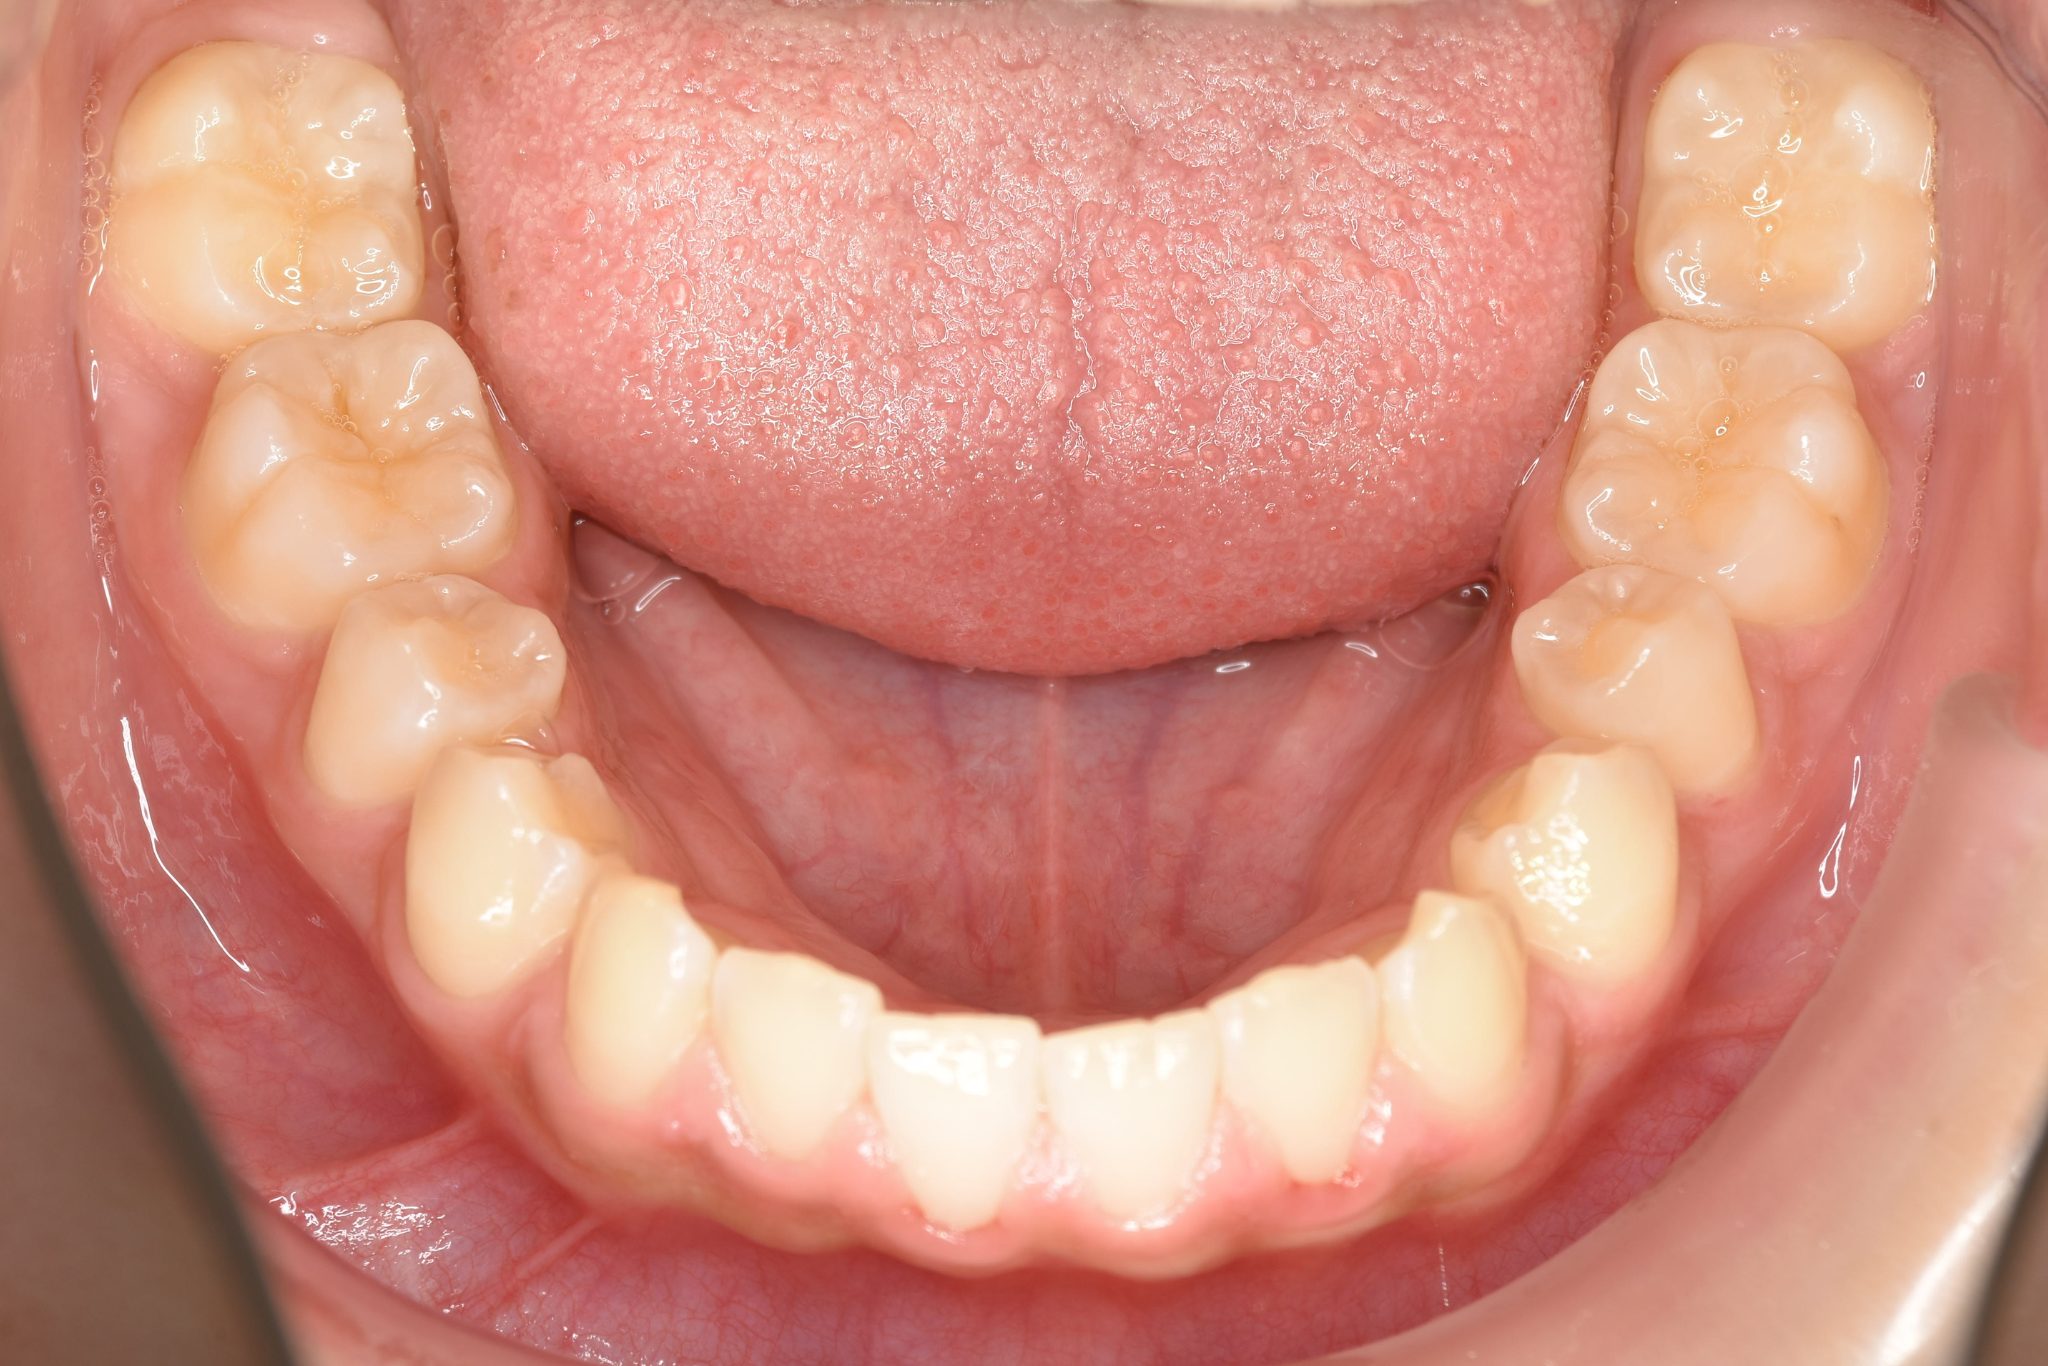

ビフォー

全顎ワイヤー矯正 症例_108

主訴 受け口|前歯がかみ合わない|顔貌

施術内容 小児矯正1期治療

治癒期間 3年11ヶ月間

費用 498,960円(税込)